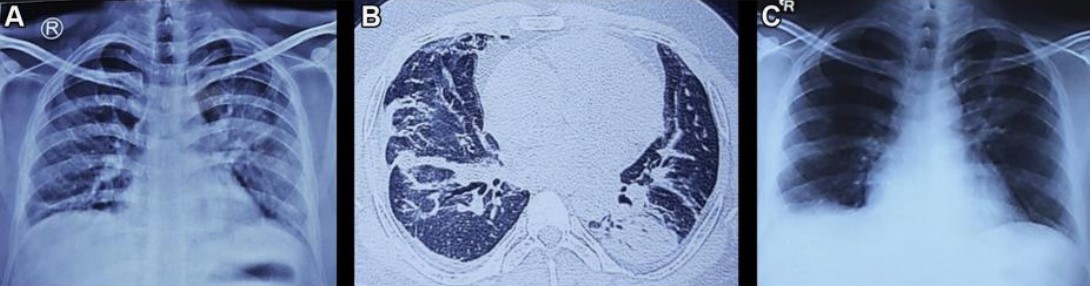

患者血液檢查結果見表1?;颊?strong>白介素6(IL-6)升高,53pg/mL,鐵蛋白水平升高,515 ng/mL。胸片顯示左側中區和下區實變(圖2A)。心電圖顯示為竇性心動過速。床旁超聲心動圖檢查顯示左心室整體運動功能減退,射血分數降低40%~45%。胸部CT掃描顯示雙側不均勻的毛玻璃樣斑塊,以支氣管血管周圍為主,實變累及左下葉上段(圖2B)。腹部超聲與CT掃描及神經傳導檢查結果均正常。

圖2 A.患者入院時的胸片;B.入院后行胸部CT掃描;C.患者出院時的胸片

最初對患者進行補氧、理療和抗凝治療。在收到第一份血清降鈣素原報告前,醫生使用單劑量廣譜抗生素治療患者。并進行靜脈注射糖皮質激素(1 mg/kg潑尼松龍)和呋塞米(120 mg,分三次給藥)治療。同時監測患者液體出入量,平均動脈血壓維持在> 65 mm Hg?;颊咧饾u進行全天頻繁的被動和主動活動。住院的最初兩天患者發作了兩次低熱,第三天起患者退熱,并且其虛弱和低氧血癥開始改善,至第7天逐漸改善至就診前狀態。患者下肢肌力也恢復,氧飽和度恢復至99%,影像學異常也消失(圖2 C)?;颊叱鲈簳r活動自如,醫生建議其口服糖皮質激素2周。